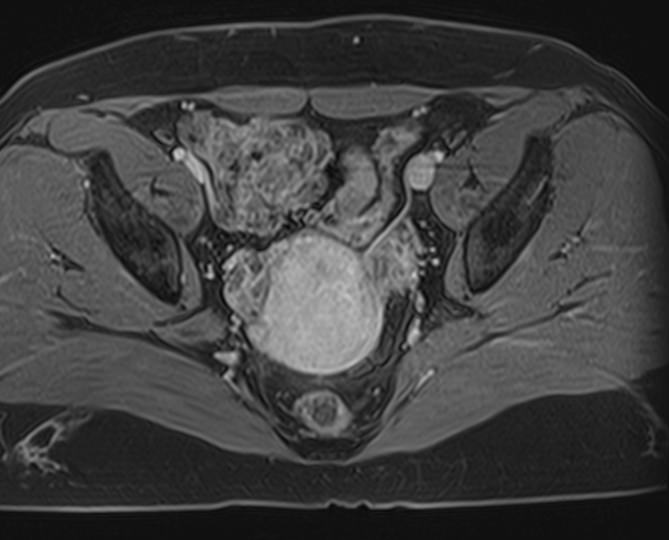

Стандартная МРТ яичников без контрастирования дает детальную информацию о состоянии яичников и окружающих тканей, но при необходимости уточнения патологических изменений, при проведении дифференциальной диагностики, внутривенно вводится контрастное вещество.

С помощью контрастного усиления повышаются шансы обнаружить минимальные изменения в органах, так как контраст избирательно фиксируется в патологических очагах, давая яркое свечение. В первую очередь, речь идет о выявлении опухолей на самых ранних стадиях развития, что имеет решающее значение в плане прогноза для жизни и здоровья пациентки.

Для контрастирования применяются препараты, содержащие соли химического элемента гадолиния (Омнискан, Гадовист и др).

• Новообразования яичников (кисты, фибромы, рак);

• Признаки доброкачественного или злокачественного характера опухоли;

• Врожденные аномалии развития придатков;

• Признаки синдрома поликистозных яичников;

• Вовлеченность в опухолевый процесс соседних органов.